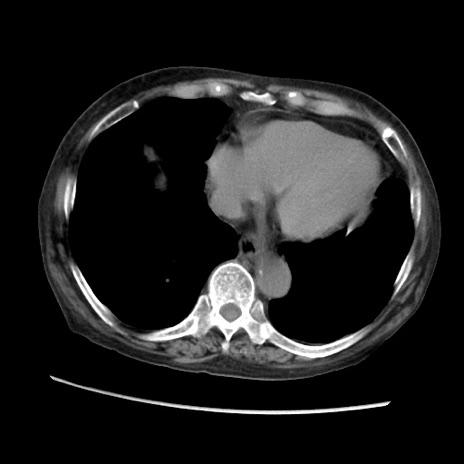

矢状断像